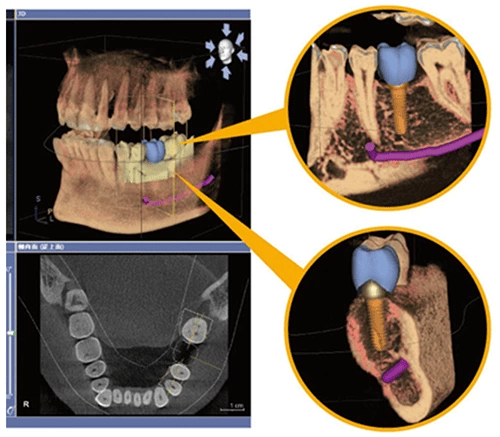

1. 3D數位植牙 德國西門子3D電腦斷層掃描

在一個診次內就可以取得全口口腔的所需要資訊,讓醫師能更精準的知道患者口腔內的狀況,不僅是骨頭內部的問題、牙床的形狀、立體化測量骨頭長度及厚度,還可以正確知道神經管、鼻竇與血管的確切位置,且在手術前做完善的治療規劃,同時可透過電腦畫面呈現,讓患者了解自身的口腔條件。最重要是患者能享受安全、舒適的數位植牙過程。